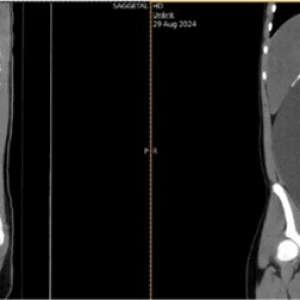

Внезапная головная боль на фоне нарушения целостности спинно-мозгового канала

Женщина, 50 лет

Обратилась в отделение неотложной помощи с жалобами на пульсирующую головную боль, которая мучила её в течение 10 дней. Впервые боль появилась остро, пациентка говорит, что в этот момент ощутила "хлопок" в спине.

Головная боль усиливалась в вертикальном положении и ослабевала в горизонтальном.

При осмотре, в том числе офтальмологическом, патологии выявлено не было.